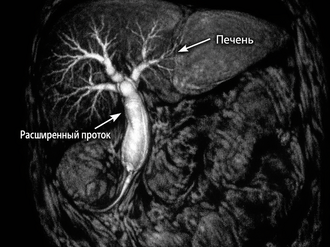

Инструментальная диагностика: УЗИ, КТ, МРТ, ЭРПХГ и их роль

Применение различных методов визуализации

Инструментальные методы позволяют визуализировать желчный пузырь и протоки:

• УЗИ органов брюшной полости: первый этап скрининга. Позволяет выявить расширение протоков и наличие камней.

• КТ и МРТ: дают более детальную информацию о структуре печени и поджелудочной железы.

• МРХПГ (магнитно-резонансная холангиопанкреатография): «золотой стандарт» неинвазивной визуализации желчных путей.